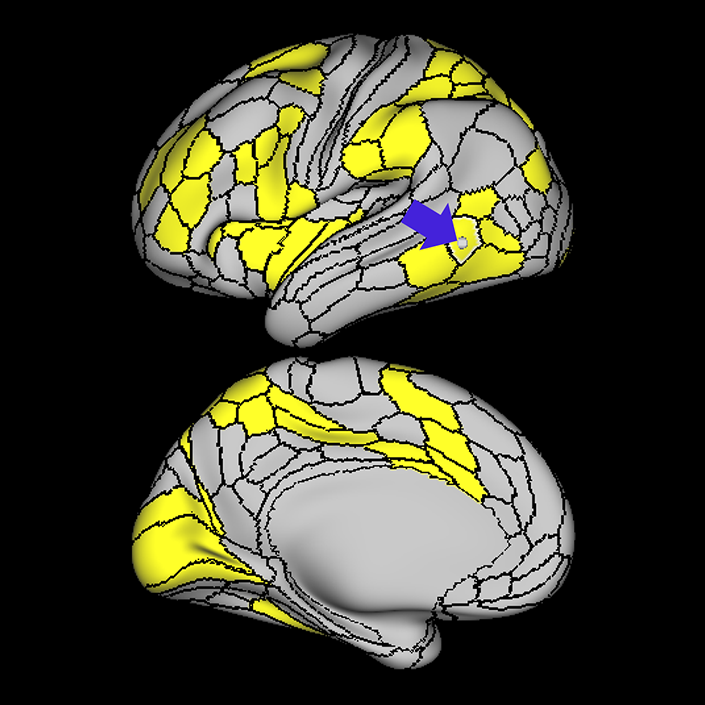

Language Network

Why we think this network is worth considering in decision making:

Disturbances of language have been linked to anatomic disruption of the human language network architecture for nearly 150 years.

Evidence that this network is responsible for useful function in humans:

While details regarding its exact organization are still in refinement, the basic details regarding the anatomy of the human language system have been non-controversial for many decades, and there is a long and robust history of using models of the language system in clinical decision-making spanning back a very long time.

Consequences of damage to this network:

Evidence that damaging this network causes neurological decline.

Several studies demonstrated aphasic impairment as a result of damage to this network in stroke patients, epilepsy patients, and tumor patients.12,13,14

Lately, speech network has been successfully mapped using rs-fMRI in an aphasic patient with left temporal tumor even in the absence of cognitive function. In the study, patient was scanned before and after a seizure that causes aphasia for several days.15 In aged patients it was found that higher functional connectivity in the left language areas associated with higher scores in behavioral tests, this finding suggests a role for functional preservation in these areas.16